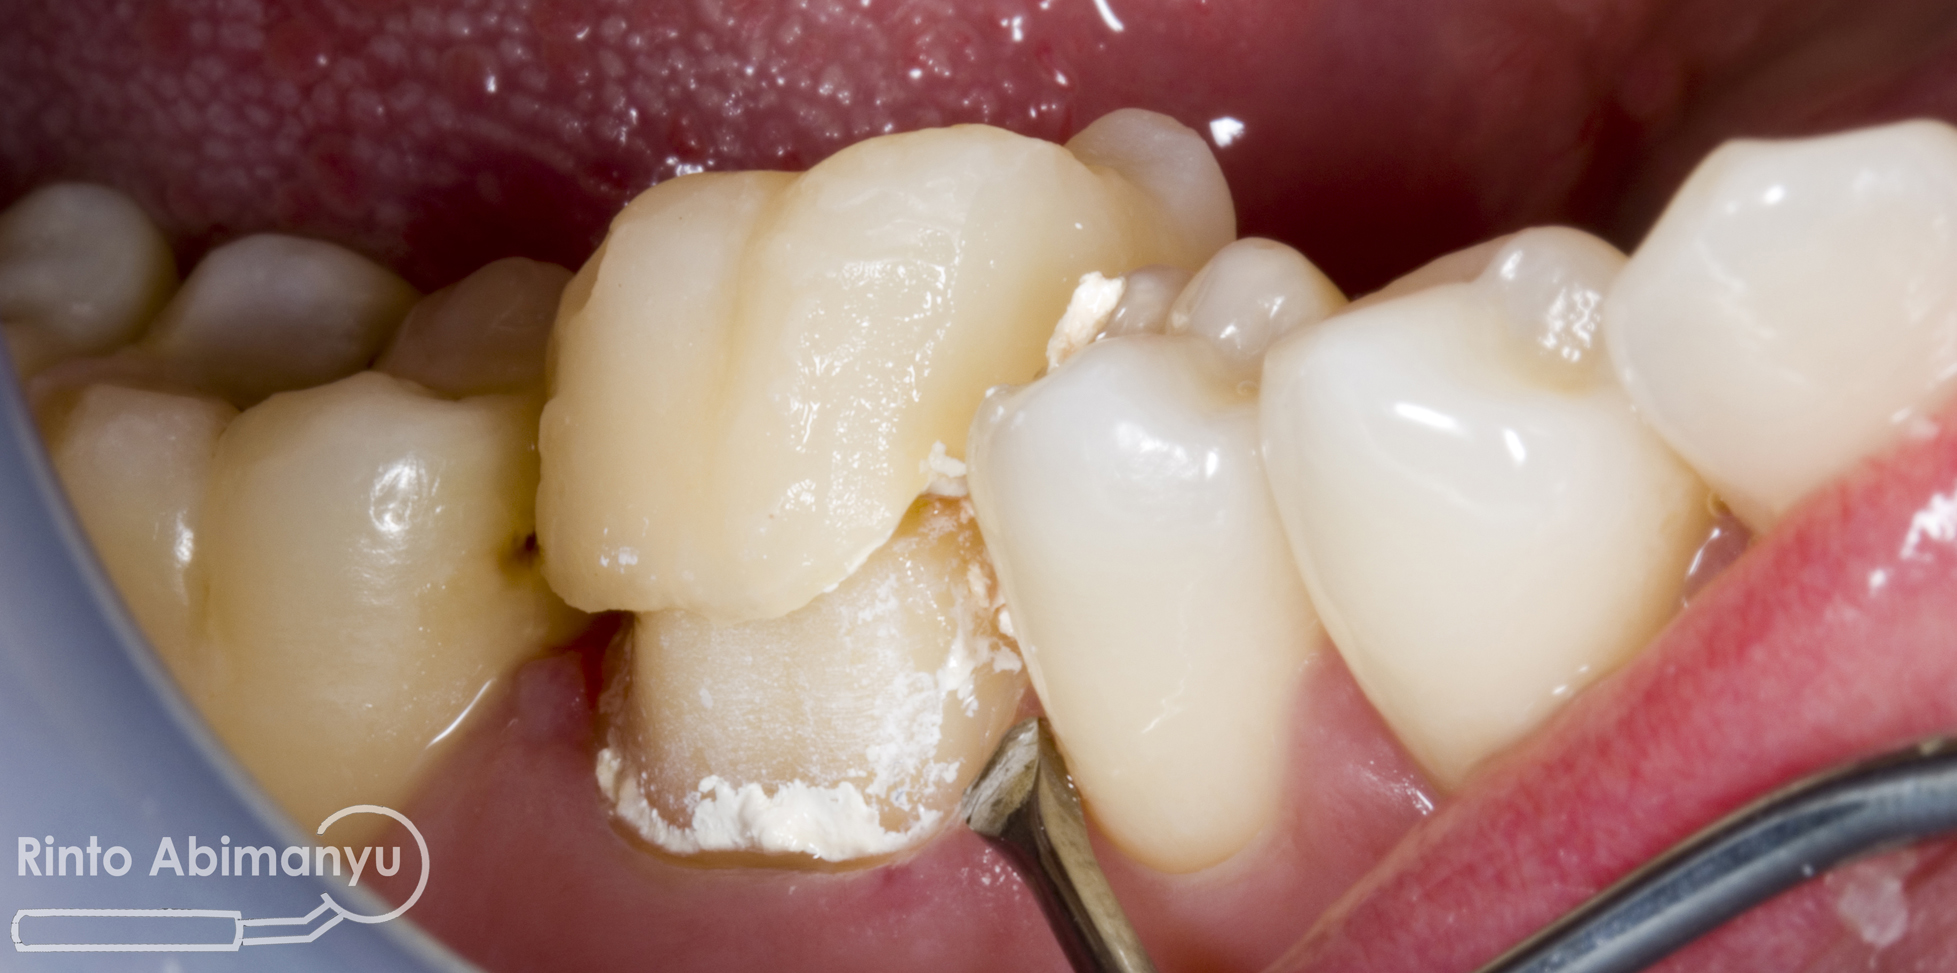

Saat pasien datang crown sementara dilepas, dan semen yang tersisa dibersihkan dengan skeler dan brush…

Dilakukan percobaan crown, dicek retensi dan resistensi, integritas tepi, titik kontak, oklusi dan warna… setelah semua tidak ada kendala maka siap dilakukan penyemenan… Semen yang dipakai adalah GIC Fuji I (GC)..